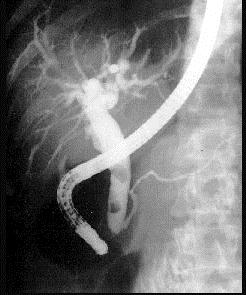

下列ERCP检查最佳的诊断是 ( )A、肝内外胆管结石B、胆囊息肉C、胆总管结石D、肝内胆管结石E、胆囊结石

问题 下列ERCP检查最佳的诊断是 ( )

选项 A、肝内外胆管结石 B、胆囊息肉 C、胆总管结石 D、肝内胆管结石 E、胆囊结石

答案 C